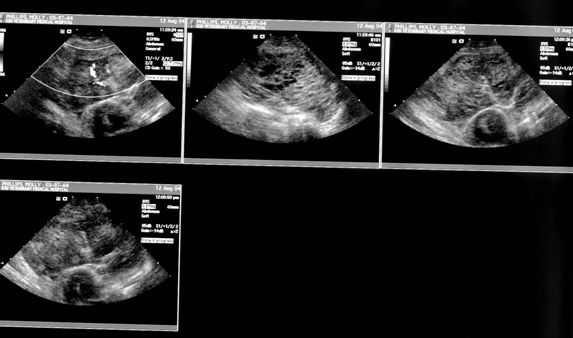

Ultrasonographic Findings:

A heterogeneous mass was identified in the left hemithorax. There was a small amount of aerated lung identified in the caudodorsal left hemithorax. There were multiple cavitary like regions identified within this mass which was immediately adjacent to the heart and the cranial mediastinal vasculature.

Impressions:

Rule outs for the pulmonary mass involving the left cranial lung lobes should include granuloma, neoplasia, with lesser consideration given to hematoma and torsed lung lobe.